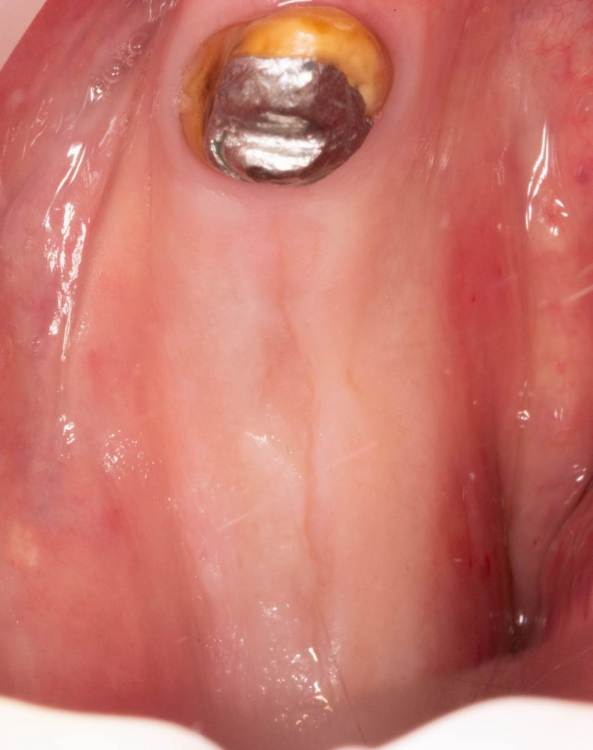

А вот снизу вариантов кроме одностороннего съёмника или имплантации не было. Поэтому план: удалить 4.6, выскрести всю гадость, имплантация 4.5-4.7 и мостовидная конструкция в будущем, также планировал работу с десной, но скелетировав кость понял, что биотип толстенный и нет в этом смысла.

Пациент бросающий курильщик (хорошо хоть не барабанщик), поэтому заглушка, швы. Хотя торк около 50, имплантиумы, 4.5 на 10 и 8 соответственно.

Поставил фдм, без как-либо пластик.

Коллеги, как вы "ищите" свои импланты? и какими методиками чаще проводите раскрытие?